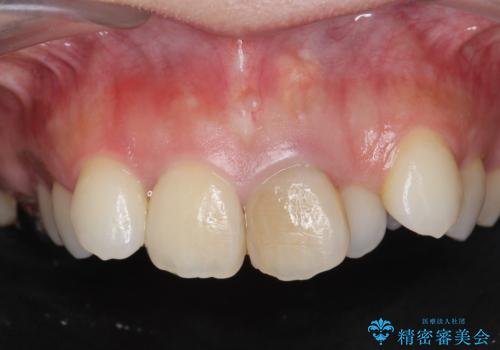

[前歯の変色] 前歯の見た目を改善したい

![[前歯の変色] 前歯の見た目を改善したいの症例 治療前](https://seimitsushinbi.jp/wp/wp-content/uploads/2021/05/510b0093313ff75fbcb626419a0f3045-500x350.jpg?v=1622180184)